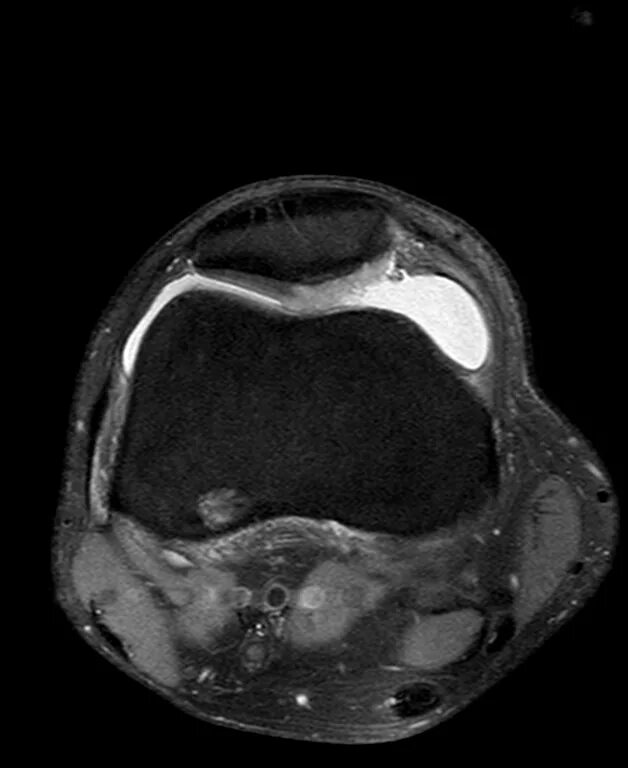

Повреждение хряща по outerbridge